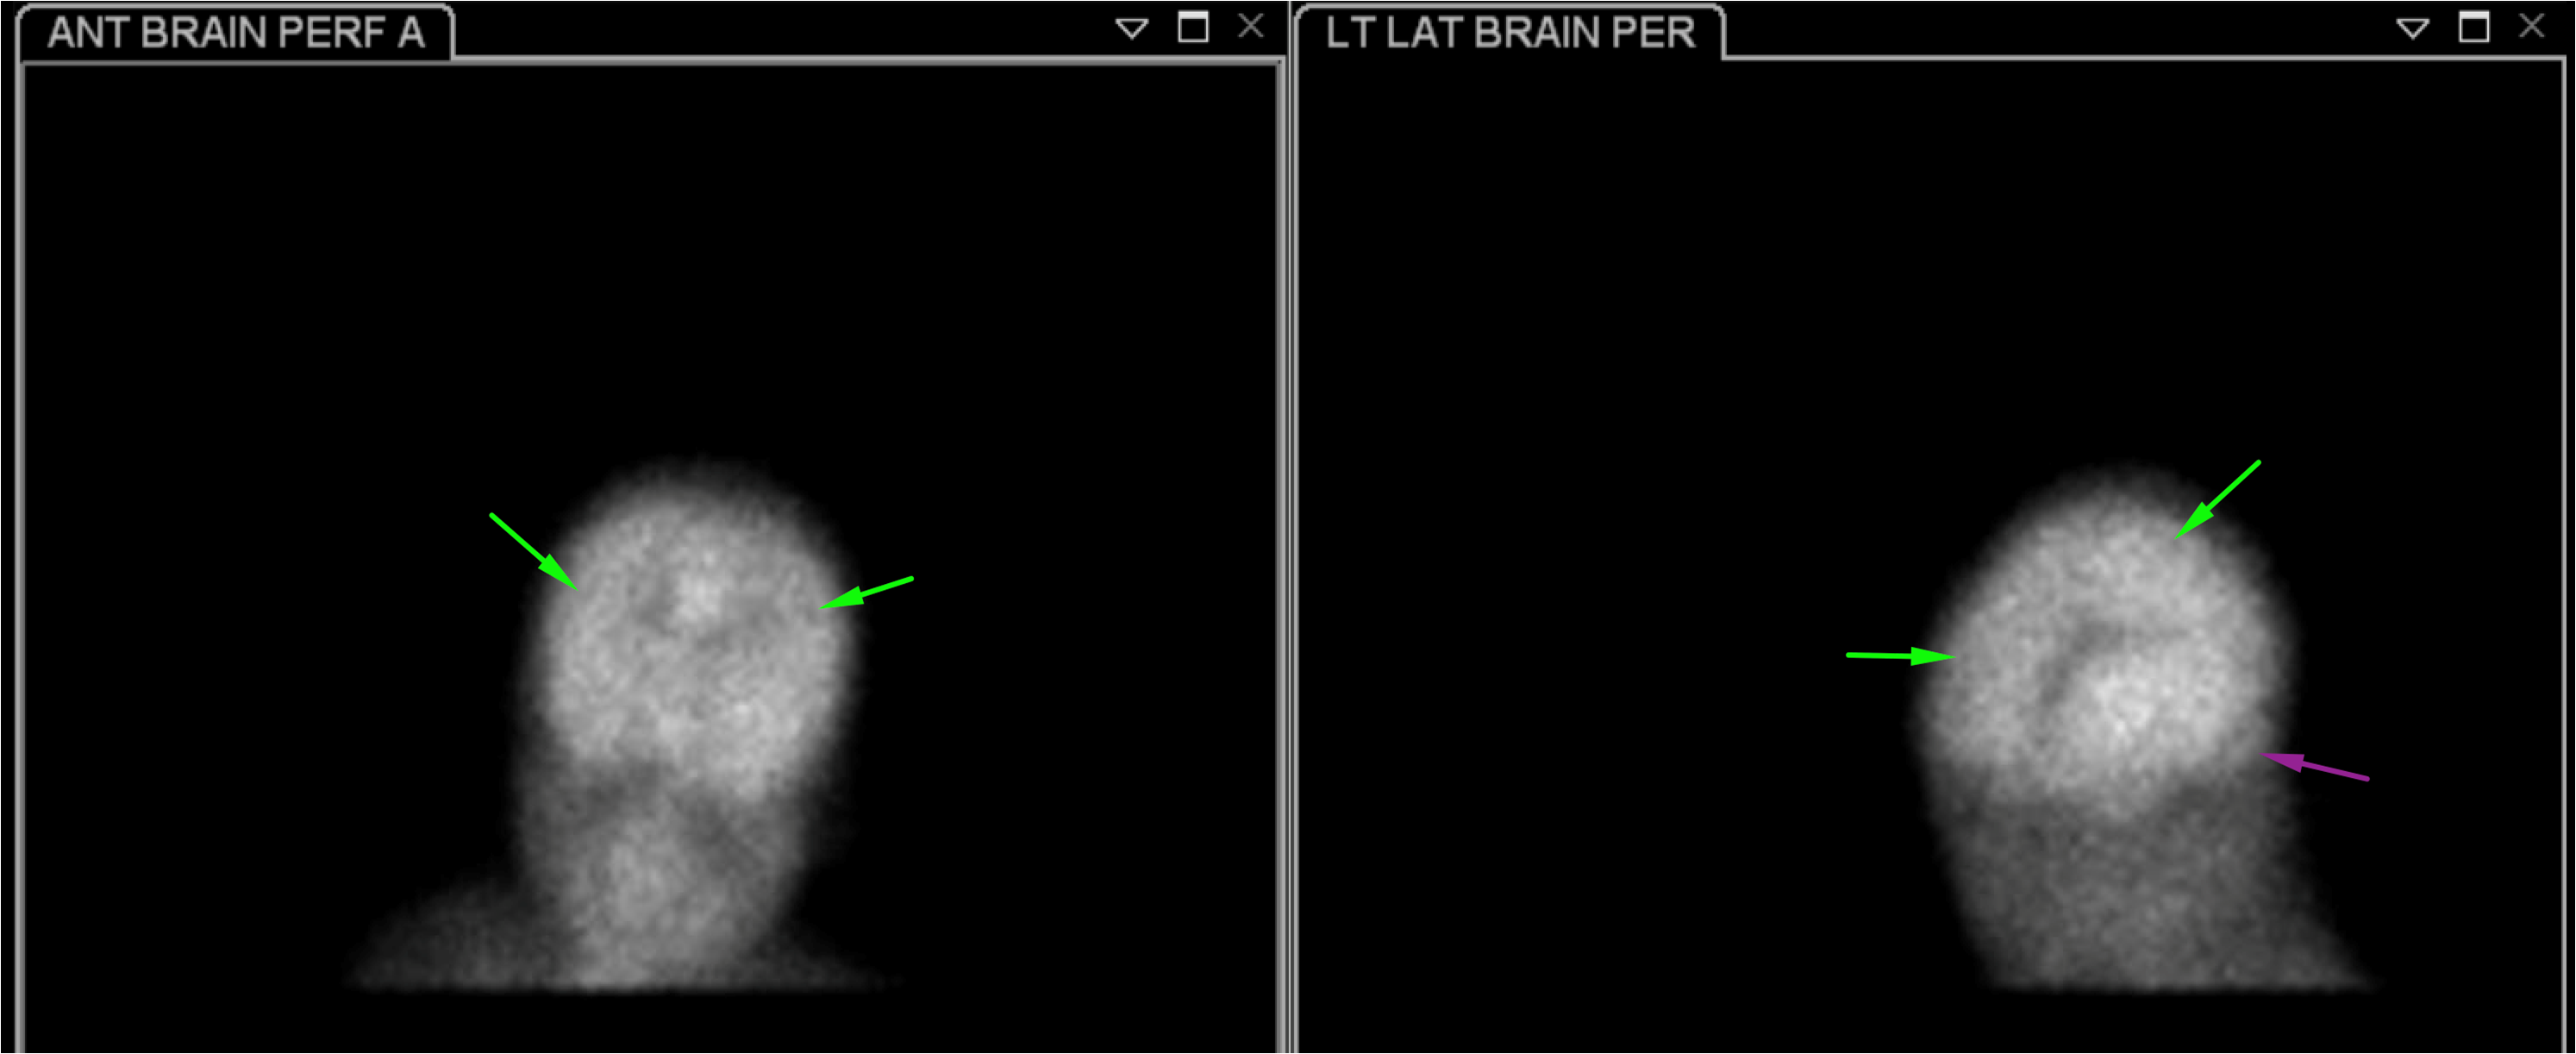

Indication: Trauma, evaluate for brain death

Radiotracer: Tc99m ECD

Sample ReportBrain perfusion is present in the bilateral cerebral cortex and cerebellum. These findings are not consistent with brain death.